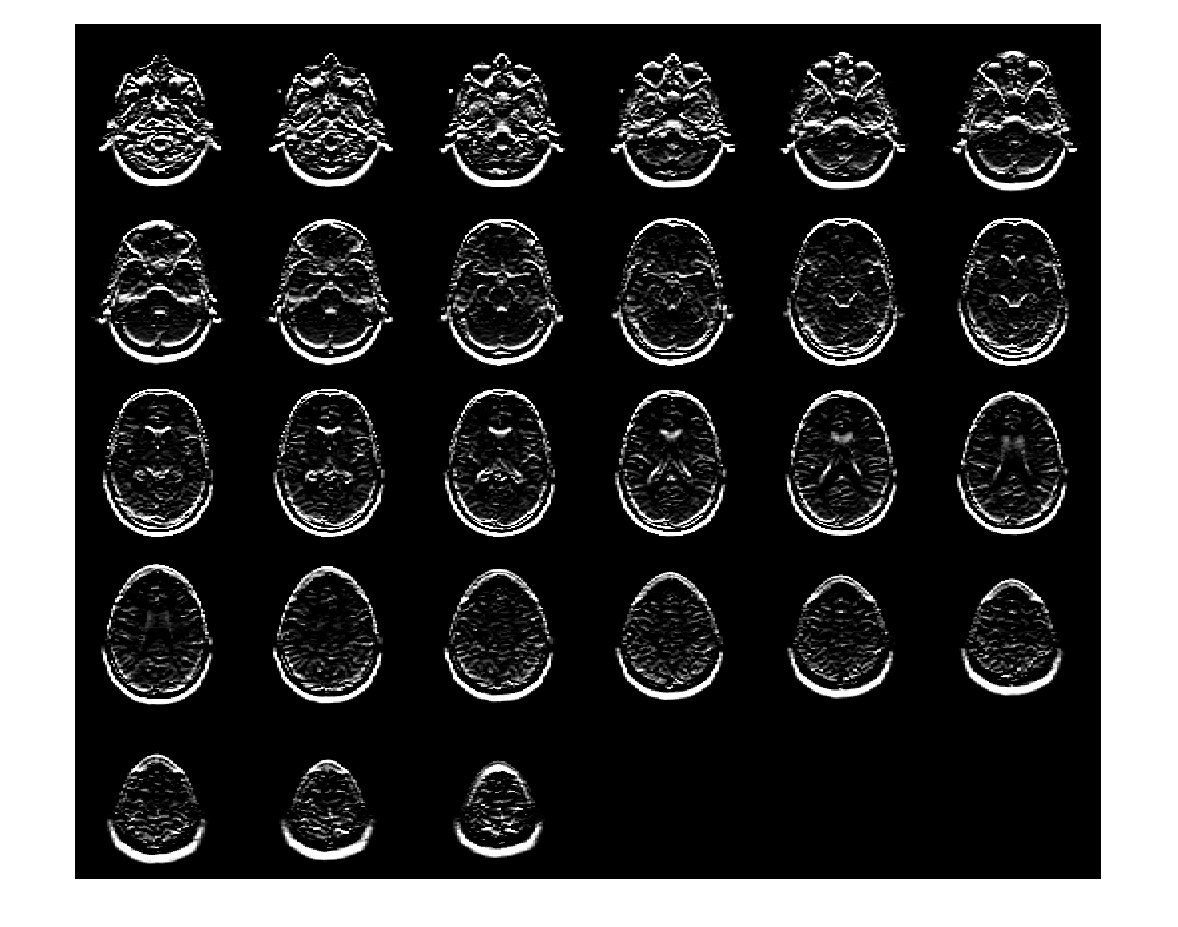

Создайте 3-D фильтр Sobel, который обнаруживает горизонтальные ребра в объеме. Горизонтальные ребра появляются, где существует большая величина градиента в направлении Y, поэтому задайте направление фильтра Sobel как 'Y'. Фильтр Sobel сглаживает градиент в x и z направлениях.

H = fspecial3('sobel','Y');

Отфильтруйте объем с 3-D фильтром Sobel.

edgesHor = imfilter(V,H,'replicate');

Отобразите плоскости отфильтрованного объема.

montage(edgesHor)

Figure contains an axes object. The axes object contains an object of type image.